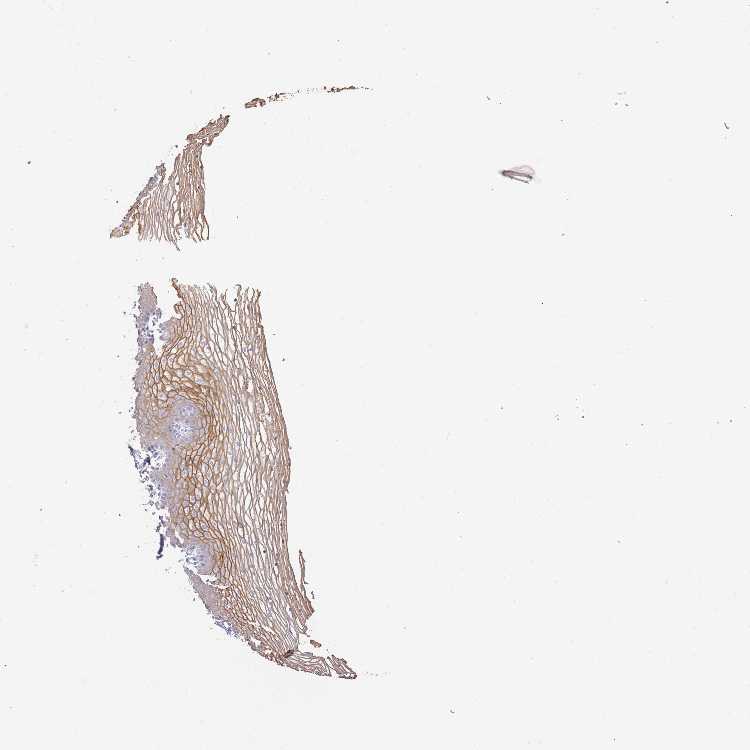

TISSUE PRIMARY DATA VAGINA Show tissue menu

VAGINA - Antibody stainingi

Antibody staining in the annotated cell types in the current human tissue is reported as not detected, low, medium, or high, based on conventional immunohistochemistry profiling in selected tissues. This score is based on the combination of the staining intensity and fraction of stained cells.

Each image is clickable and will lead to virtual microscopy that enables deeper exploration of all samples and also displays staining intensity scores, fraction scores and subcellular localization as well as patient and tissue information for each sample.

Antibody HPA041874Antibody HPA043317

Squamous epithelial cells HighHigh